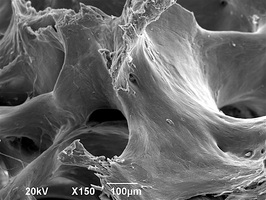

Биоимплантаты аллогенные стерильные губчатые механически и и ультразвуком обработанные.

По внешнему виду представляет собой пористый губчатый блок номинального размера.

2. Поверхность и структура материала для изготовления биоимплантатов